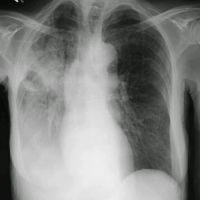

Ambulant erworbene Pneumonie

Jede Pneumonie, die durch einen Erreger im außerklinischen (ambulanten) Bereich erworben wurde, wird als "ambulant erworbene Pneumonie" bezeichnet. Auf Grund der Inkubationszeit der wichtigsten Erreger werden alle Pneumonien, die innerhalb der ersten beiden Tage nach einer stationären Aufnahme diagnostiziert werden, auch in diesem Sinne als ambulant erworbene Pneumonie bezeichnet und unterliegen ebenfalls der Dokumentationsverpflichtung.